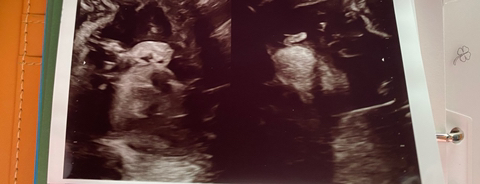

임신 23주 소이증 진단..

지난번 초음파에서 귀가 짝짝이라고 했는데

오늘 정밀초음파를 보니 귀가 많이ㅡ차이나더라구요

왼쪽귀가 작아서 소이증 진단 받앗어요